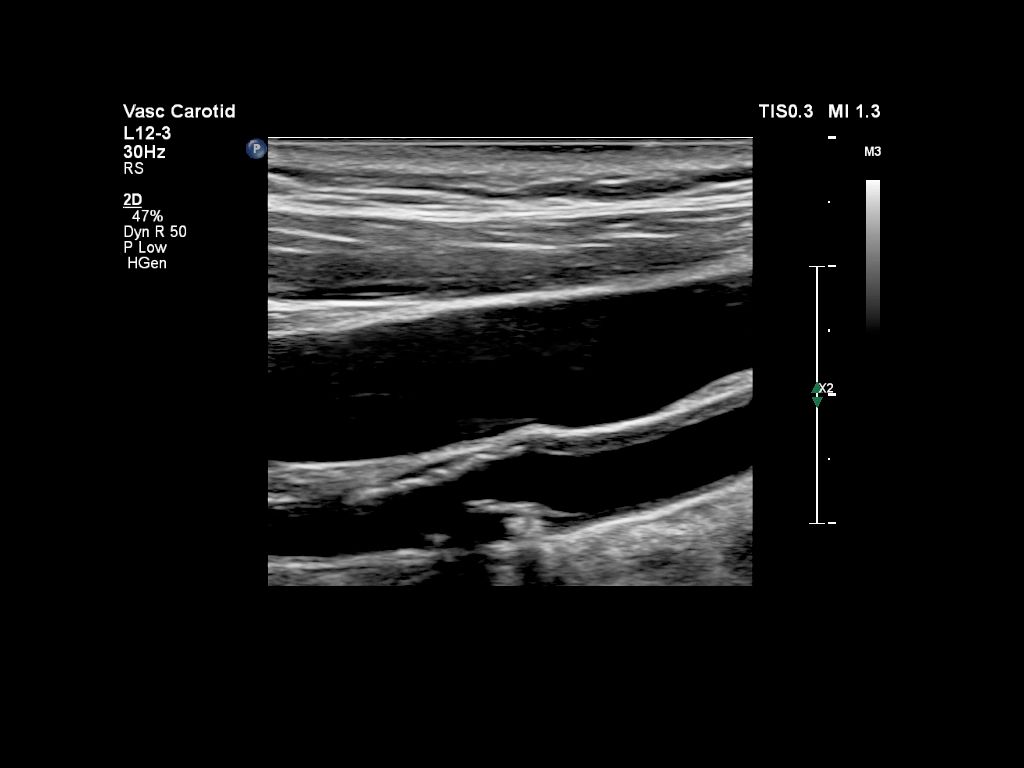

Функции для исследования сосудов

- VPQ (Vascular Plaque Quantification) - функция автоматического количественного анализа атеросклеротических бляшек в сонной артерии в режиме 3D. Функция автоматически вычисляет количество бляшек, площадь просвета сосуда и идеально подходит для полноценного анализа состава атеросклеротических бляшек

- IMT - функция для автоматического расчета комплекса интима-медиа

- ROI - технология для согласованности и надежности акустических измерений для более простого анализа зоны интереса при контрастной визуализации, TDI и цветового допплеровского сканирования.

- Auto Doppler - автоматическая настройка импульсно-волнового допплера и ЦДК

- VPQ (Vascular Plaque Quantification) - функция автоматического количественного анализа атеросклеротических бляшек в сонной артерии в режиме 3D. Функция автоматически вычисляет количество бляшек, площадь просвета сосуда и идеально подходит для полноценного анализа состава атеросклеротических бляшек

- Модуль Q-App для определения толщины комплекса интима-медиа

- Функция Auto Doppler для исследования сосудов

- Функция количественного анализа бляшек VPQ